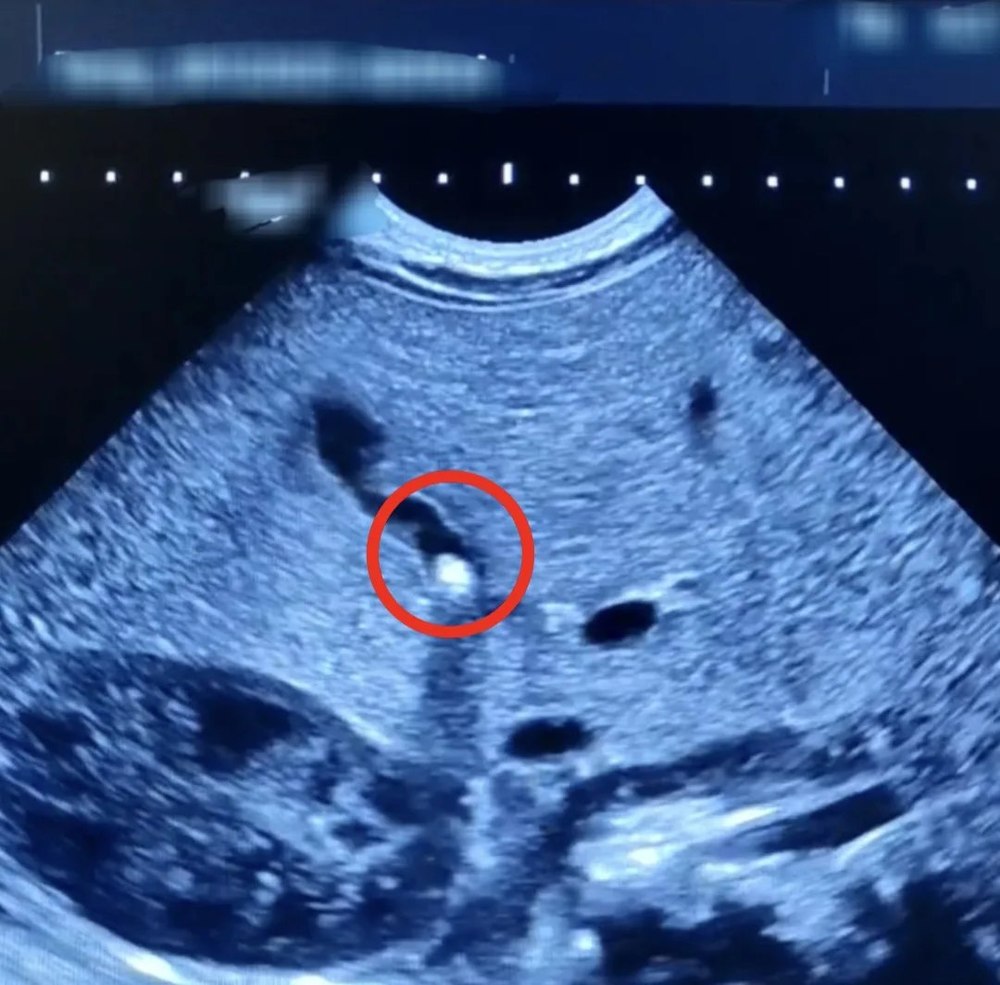

В Балакове врачи нашли у полуторамесячного младенца камень в жёлчном пузыре. Об уникальном случае сообщается в Телеграм-канале местной городской клинической больницы.

В декабре мальчик поступил в стационар с жалобами его матери на плохую прибавку массы тела и желтушное окрашивание кожи и склер. При обследовании выяснилось, что желчный проток частично закрыт камнем небольших размеров. Ребёнок получал в больнице необходимое лечение. Врачам удалось улучшить отток желчи и добиться стабильной прибавки в весе, которой не наблюдалось ранее. Пациент выписан домой и находится на амбулаторном наблюдении.